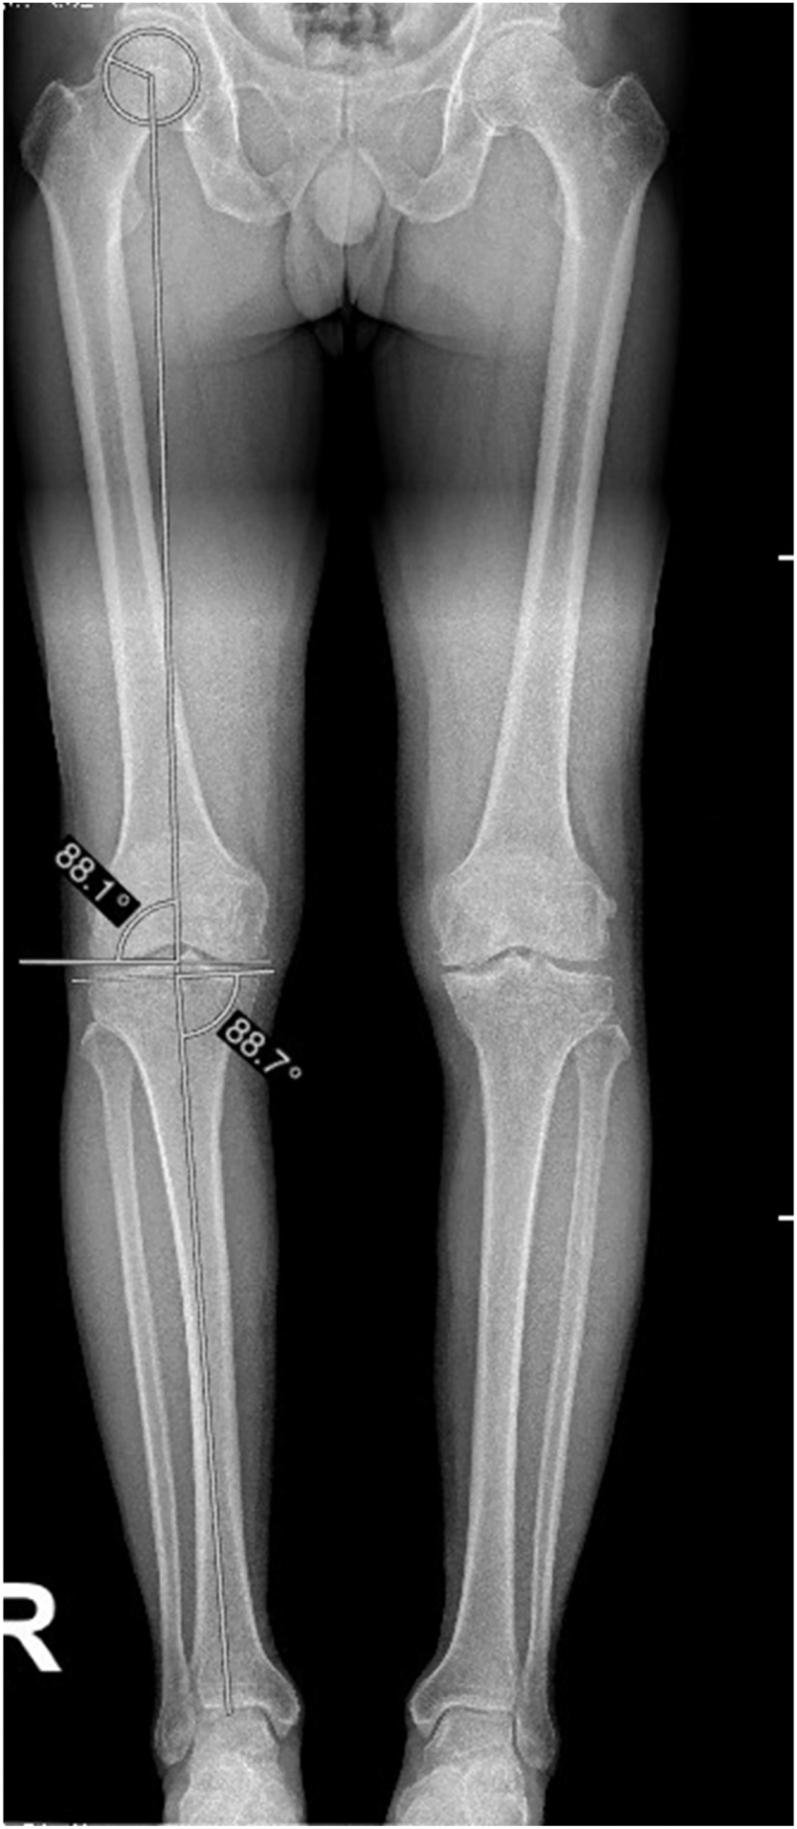

This review presents a standardized, stepwise method for biplanar radiographic analysis of knee alignment, integrating both coronal and sagittal measurements for use in arthritic and non-arthritic knees. It critically compares leading classification systems, including the coronal plane alignment of the knee (CPAK) and the functional knee phenotype classifications. While CPAK provides a simplified 2D coronal model, the functional phenotype system offers a more granular, 3D approach that includes segmental deformities and has recently been expanded to incorporate laxity parameters. Sagittal plane parameters - including posterior tibial slope and femoral component flexion/extension - are essential for comprehensive alignment assessment. These factors influence implant positioning, knee kinematics, and postoperative function. The review outlines preferred measurement techniques, highlighting the value of long-leg weight-bearing radiographs and discussing the limitations and variability of 2D versus 3D imaging approaches. Incorporating both alignment and soft tissue behavior provides a more individualized approach to total knee arthroplasty planning and may lead to improved outcomes by better replicating native knee biomechanics.